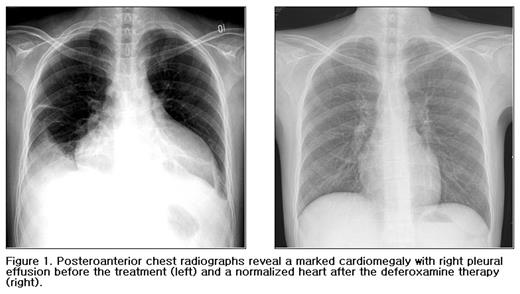

A 24-year-old male patient with hemochromatosis due to multiple packed red blood cell transfusions, was referred to our emergeny center for a treatment of severe aplastic anemia and dyspnea. He was diagnosed with aplastic anemia at the age of 11 and had developed a transfusional hemochromatosis after 5 years of multiple blood transfusions. He had dilated cardiomyopathy with ejection fraction of 4 % requiring diuretics and digitalis, multiple endocrine dysfunctions (hypothyroidism, hypoparathyroidism with hypocalcemia, cataract, and intracranial calcifications, diabetes, and gonadal dysfunction), liver dysfunction, generalized bleeding, and skin pigmentation (Fig.1-left). A total volume of packed red blood cell transfusion before deferoxamine therapy was about 96,000 ml and the number of transfused units of platelet concentrates were innumerable. He had received regular iron chelation therapy (continous intravenous infusion of deferoxamine, 50 mg/kg/day for 5 days q 3–4 weeks) for 7 years after multiple organ failures. His cytopenias and organ dysfunctions (heart, liver and skin) began to recover progressively in 2002, after four years of deferoxamine therapy. He had had complete normal ranges of his peripheral blood cell counts, heart size, and liver function two years ago (Fig.1-right & Fig.2). He has not received any transfusions for the last four years. This finding suggests that continuous deferoxamine infusion may play a role in immune regulation in addition to iron chelation effect.

Posteroanterior chest radiographs reveal a marked cardiomegaly with right pleural effusion before the treatment (left) and a normalized heart after the deferoxamine therapy (right).